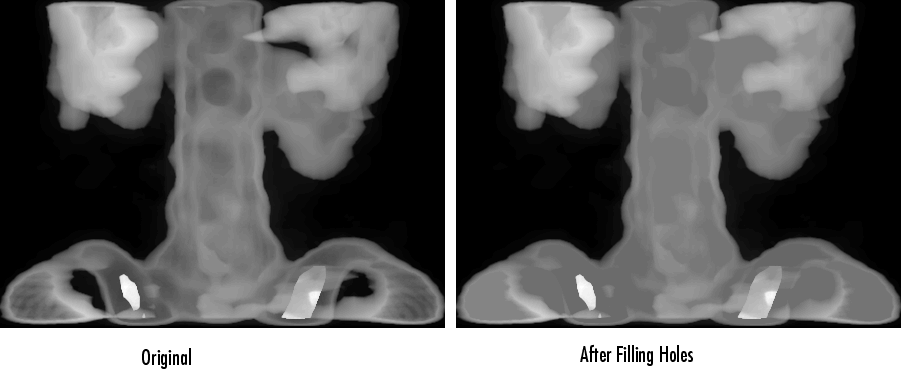

Для иллюстрации этот пример заполняет отверстия на изображении позвоночника в градациях серого.

[X,map] = imread('spine.tif');

I = ind2gray(X,map);

Ifill = imfill(I,'holes');

imshow(I);figure, imshow(Ifill)